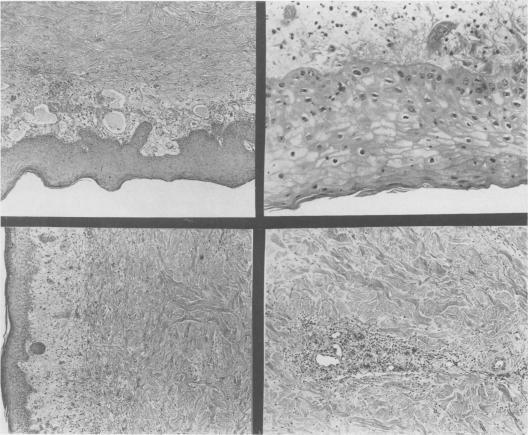

Burn following accidental exposure to high energy radiation.

Ann Surg. 1959 Feb;149(2):286-93. doi: 10.1097/00000658-195902000-00016.